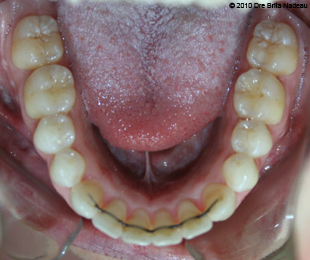

Marie-Hélène Cyr - Lower occlusal view - After orthodontic treatments and orthognathic surgeries (January 29, 2010)

January 29, 2010 - My lingual wire can easily be observed on my 6 front lower teeth.